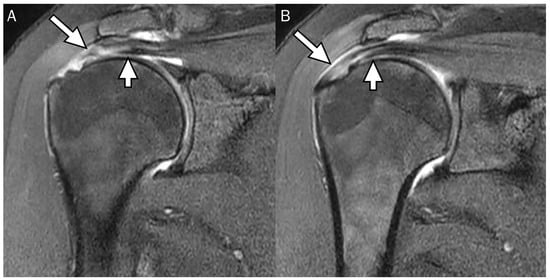

4. Radiologic Definition and Classification Using MRI

5. Radiologic Diagnosis of Delaminated Tears Using MRI